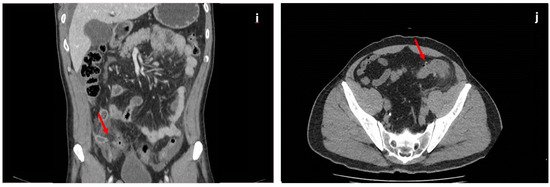

The influence of clinical information on reporting was demonstrated in a prospective blinded study that analyzed the results written before and after clinical input. Inconsistent clinical details have a detrimental effect, while accurate information improves the quality of a report [15,16,17,18]. When expert readers assess CTs, they use three techniques: drilling, scanning, and “scrilling”. Drilling refers to evaluating a stack of images by using small visual corridors that are parallel to each other and allow in-depth visualization of structures. Scanning implies using slices rather than corridors and is more suitable for organs that span horizontally, such as the pancreas. “Scrilling” is a mixed technique combining in-depth analysis with scanning and helps assess sections containing organs of different shapes and densities, such as the abdomen and pelvis [16] (Figure 2).

Figure 2.

Techniques for multiple-target searching during CT examination. The red arrows show the direction of the visual search pattern.